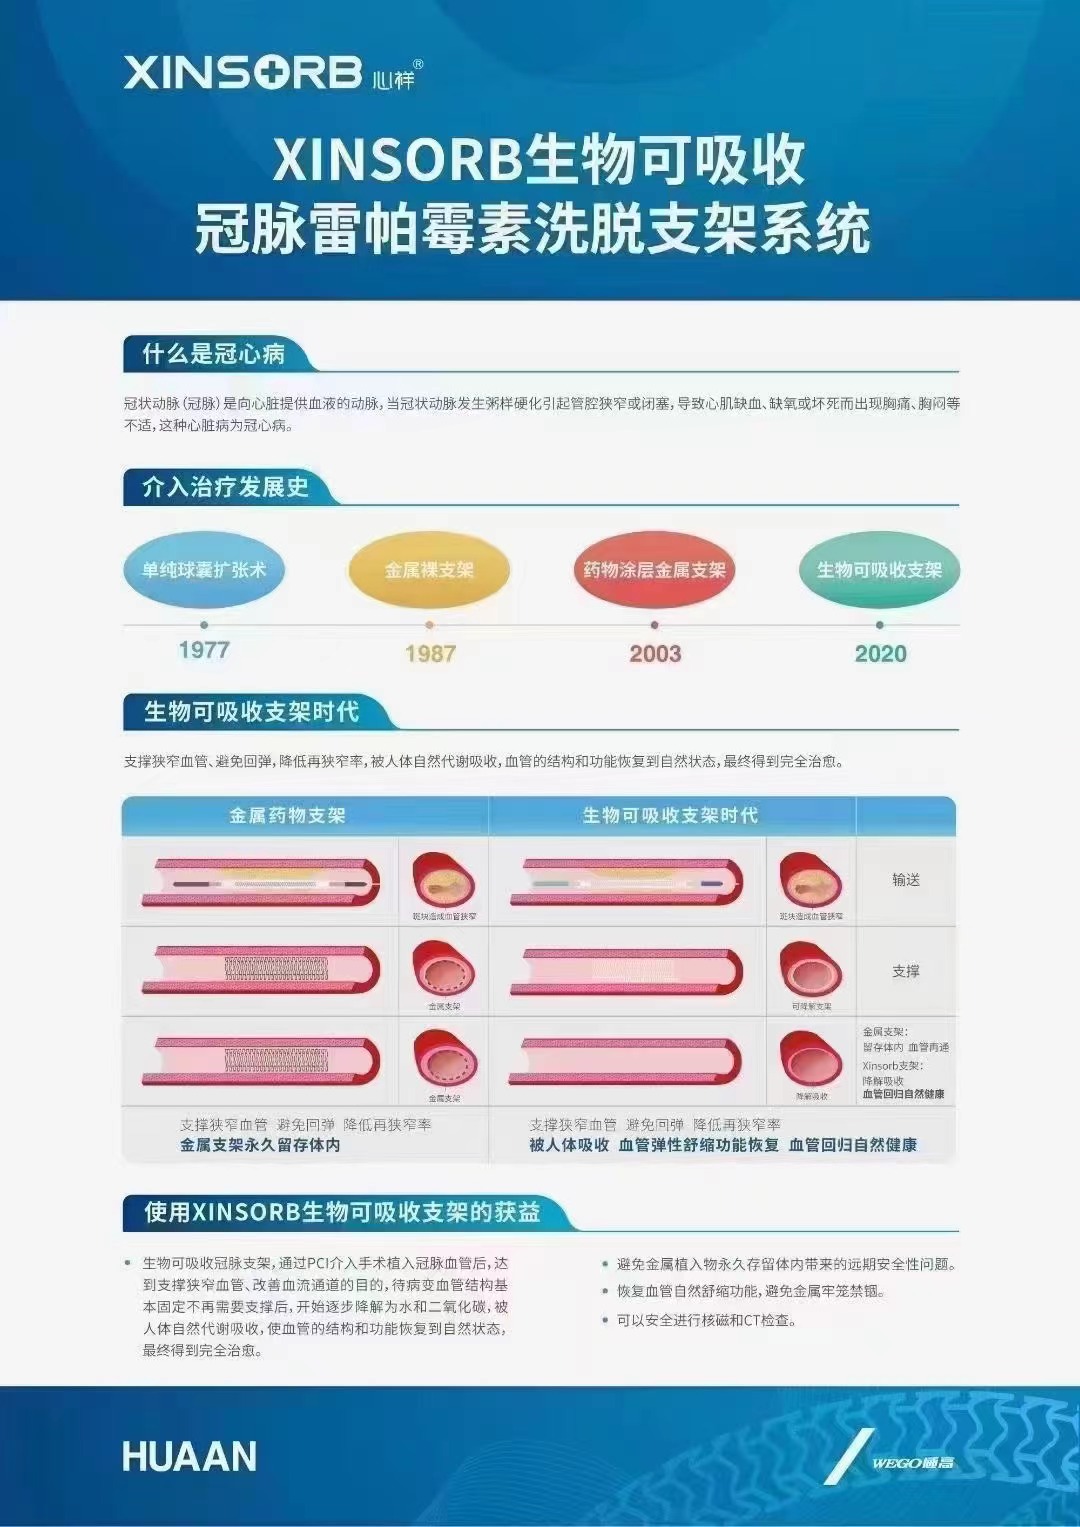

Xinsorb 生物可吸收支架和心內(nèi)科醫(yī)生共同守護(hù)您的心臟

Xinsorb 生物可吸收支架和心內(nèi)科醫(yī)生共同守護(hù)您的心臟